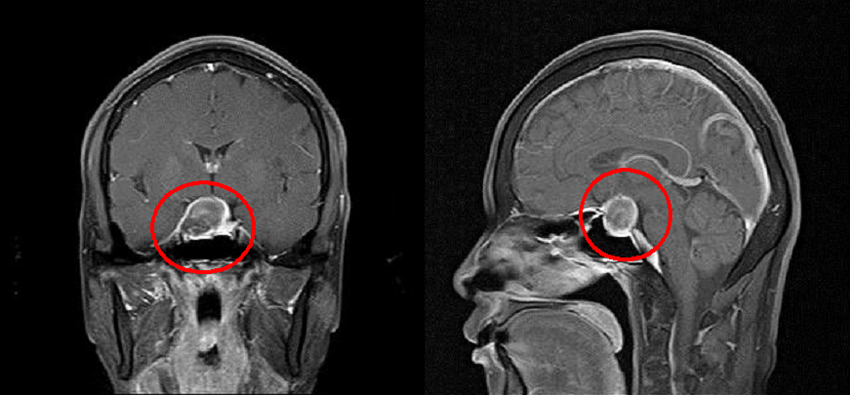

뇌하수체졸중이란 뇌하수체 선종에서 갑작스러운 경색이나 출혈로 인해 뇌하수체가 급격히 팽창하여 주위 조직을 눌러 두통, 구토, 시력 소실, 안구운동 장애, 의식 저하 등을 일으키는 임상 증후군을 의미한다. 발생 기전은 잘 알려져 있지는 않으나 종양의 성장이 혈류 공급을 초과해서 조직 괴사와 함께 출혈이 발생한다고 추측되며, 종양에 의한 혈관의 직접적인 압박, 종양 자체의 혈관이상 및 종양 내에 동맥류가 동반된 경우 등도 보고 되었다.

만약 뇌하수체졸중이 의심된다면, 가능한 빨리 두부 CT 나 MRI를 촬영한 뒤 진단된다면 응급수술로 종양을 제거해 주고, 뇌하수체 기능 저항에 대한 호르몬 치료를 시행하여야 한다.